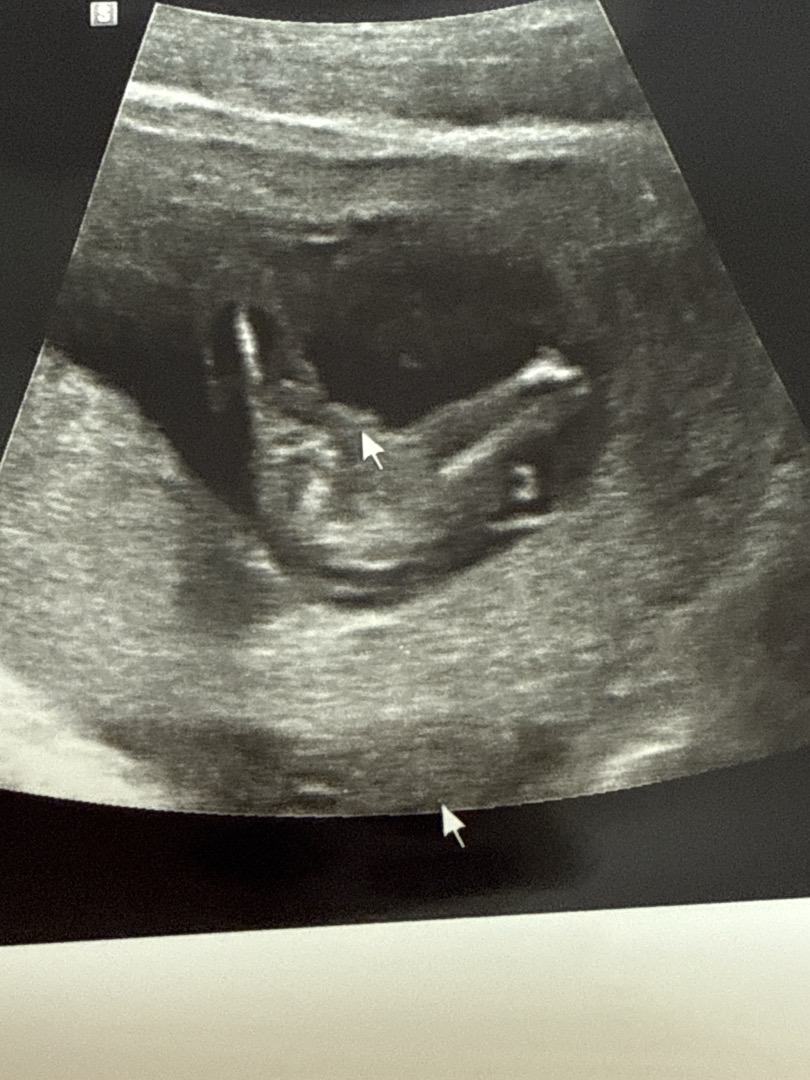

14주 성별 봐주세요

딸 같다고 하시는데 반전 있을까요??